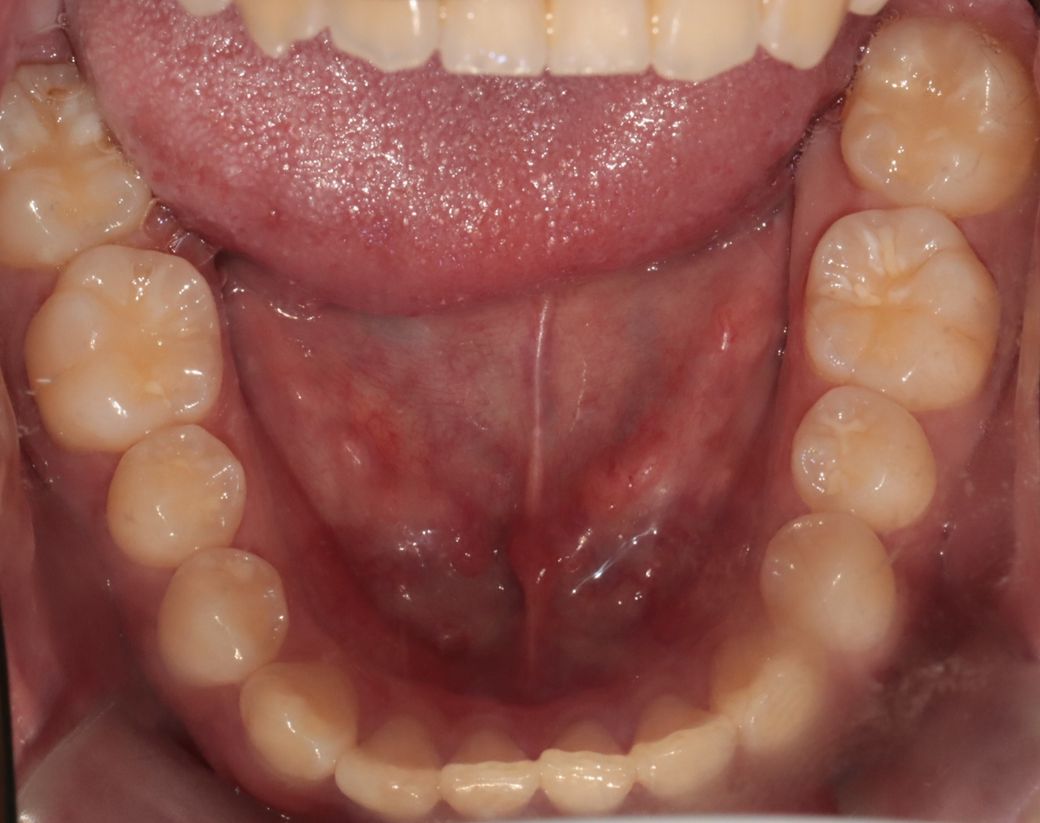

치아 앞니쪽에 반대교합이 있어서 분분교정할 생각인데 부분교정으로 치료가능해 보일까요?

앞니빼고 나머지는 괜찮아 보일까요?

윗니가 아랫니를 덮는 양또는 윗니가 앞으로 나온양이조금 적다고는 하는데 골격적 문제라 어쩔 수 없다는데 맞나요?

부분 교정으로도 어려워 보이며 전체 교정도 현재 증상을 개선하기가 쉽지 않아 보입니다. 워낙 다른 부위에 치열 상태는 나쁘지 않기 때문에 교정을 하더라도 현재 증상에 대한 개선이 어려울 수도 있어 보입니다. 또한 치열 배열 뿐만 아니라 골격적 문제가 동반되고 있어 골격적인 부분은 교정으로 수정할 수가 없습니다.

지금 정도의 골격적 부조화는 일반인들은 알아차리지 못하며 양악 등을 수술을 권하는 정도도 아닙니다.

사진상으로 보면 크게 문제가 있어보이지는 않습니다. 하지만, 기능상으로 문제가 있다면 교정을 하시거나 심미적개선을 원하신다면 교정을 하시면될것같아요.